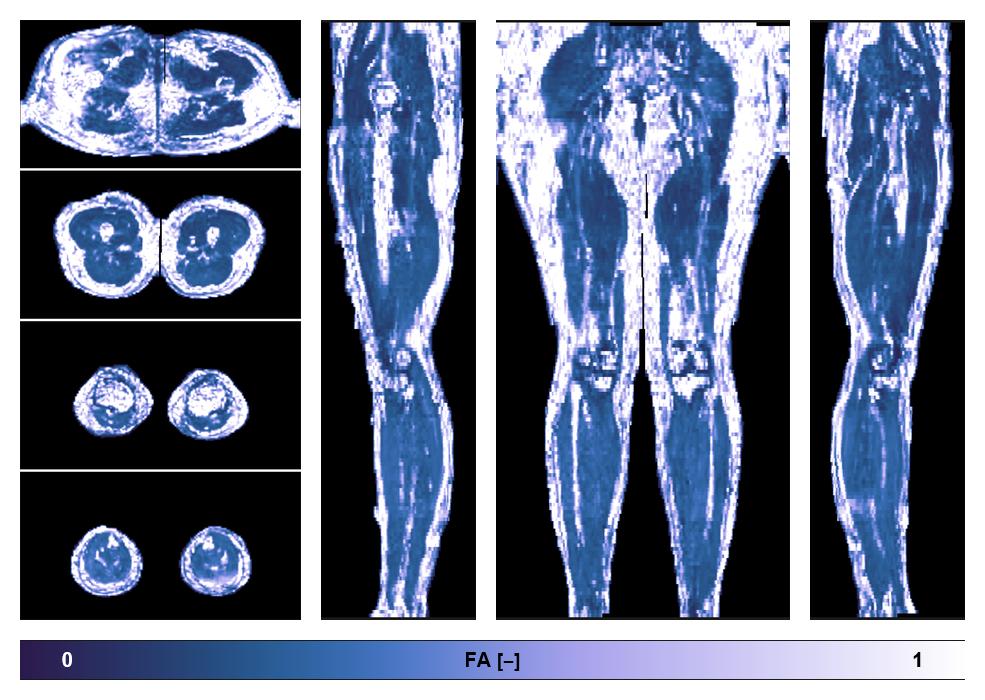

Diffusion tensor imaging

Diffusion weighted imaging with IVIM and DTI fitting to obtain muscle microstructure and muscle architecture, for information look here».

• Fractional anisotropy

IVIM corrected whole leg muscle fractional anisotropy obtained from diffusion tensor imaging.